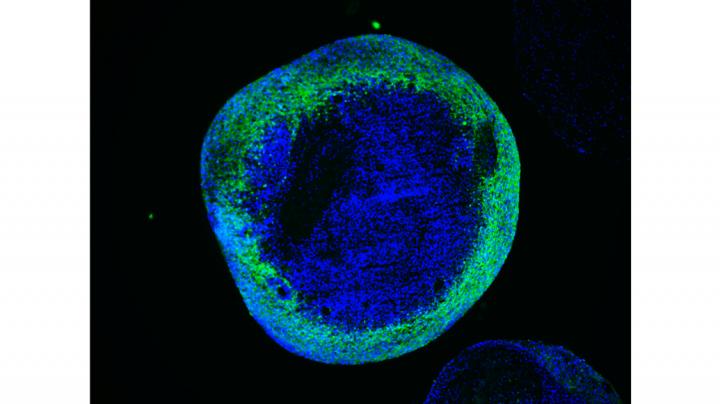

图像:在Leigh综合征患者的大脑类器官中,神经元没有正常成熟。这是由于细胞的线粒体代谢激活受损导致。版权所有:Agnieszka Rybak-Wolf博